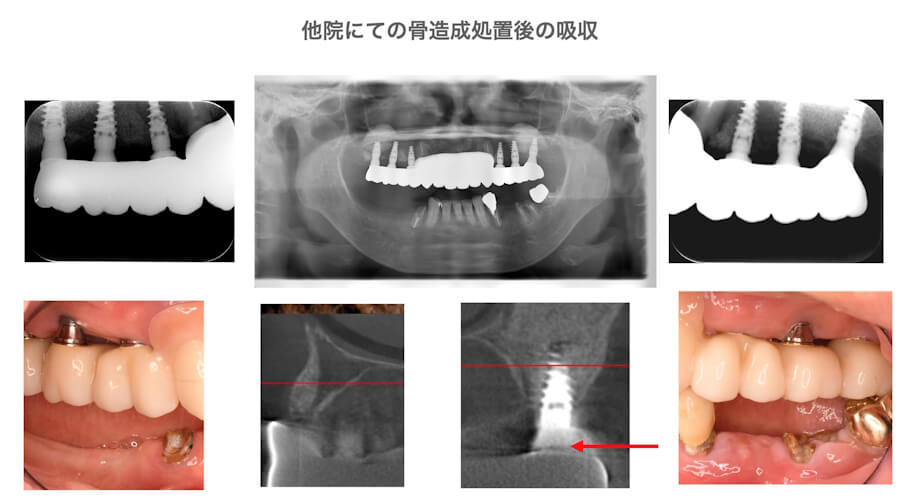

2枚目の写真は、骨造成をしてインプラントを入れたのですが、骨吸収しインプラントが露出してしまっている状態です。歯科医院に相談したところ「特に問題ない」と言われ不審に思い来院されました。